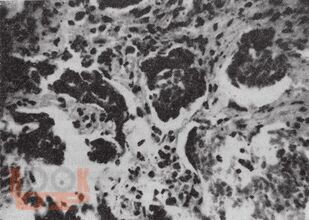

В книге суммирован опыт Государственного Научного Центра Колопроктологии МЗ РФ, Научного центра здоровья детей РАМН и Центра эндохирургии и литотрипсии по изучению и лечению одиночных полипов и множественного полипоза толстого кишечника у детей и взрослых. Приведены собственные результаты изучения патогенеза и морфологии доброкачественных полипов толстой кишки, частоты, форм и стадий их озлокачествления. Описаны и проиллюстрированы эндоскопические методы лечения полипов толстой кишки и радикальные операции при множественном полипозе. Рекомендованы необходимые сроки повторных обследований больных.